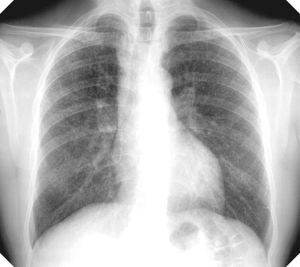

Dust from granite is particularly dangerous, because it has a high concentration of silica, which in its powdered form is extremely sharp. Some granite workers likened it to microscopic razor blades. When inhaled, silica dust scars and stiffens the lungs, which can make breathing difficult.

The danger posed by working in the sheds are borne out by Vermont Department of Health statistics: Between 1926 and 1936, stonecutters lived on average 11 years shorter than men in other professions. And a startling 73 percent of stonecutters’ deaths were attributed to silicosis and related cases of tuberculosis, a rate that was 33 times higher than for men in Barre who weren’t in the granite industry.

In 1937-38, the Vermont Department of Health tested more than 805 men who worked in the sheds and found that 45 percent of them had silicosis and an additional 18 percent had silicosis with a possible infection (probably tuberculosis).

The department started operating a mobile X-ray unit in 1951 to test workers at their workplaces during work hours. The tests showed that, though the numbers had declined sharply, 16 percent of workers still had silicosis and a little more than 2 percent had silicosis with a possible infection.